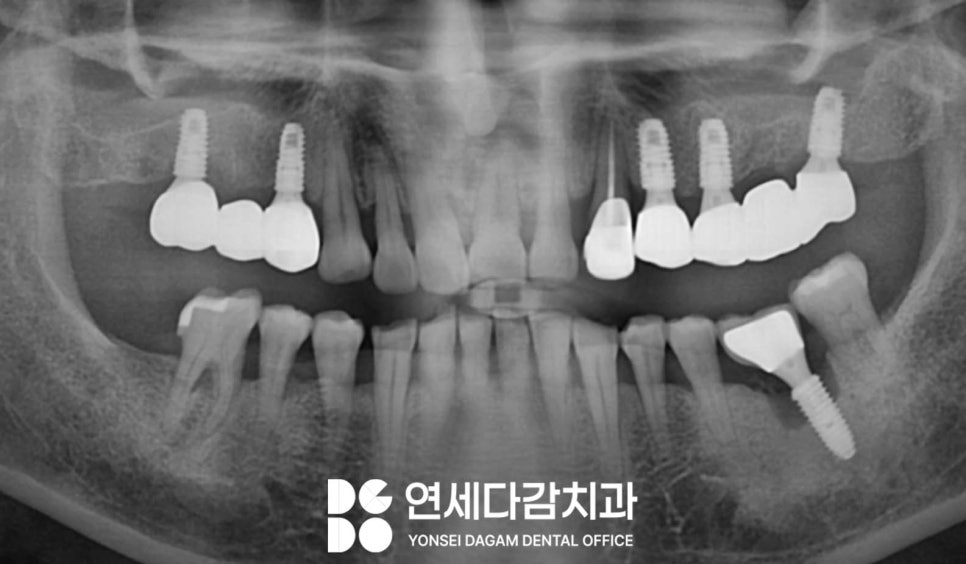

거상된 공간에 뼈이식재를

충전하여 임플란트 식립을

완료했습니다.

그 이후에는 충분한

치유 기간이 필요합니다.

안정적인 골융합을 도모하기 위해서는

충분한 기간을 가지고

관리를 하며 지켜봐야 됩니다.

정기적인 방사선 검사를 통해

골 유착 과정을 모니터링하며

고정력을 제대로 갖춘 것을 확인합니다.

골 유착이 제대로 이루어진 것을

확인한 뒤 나머지 과정을 시행하여

안정적으로 마무리할 수 있었습니다.

그 결과 문정동 치과 에서 표시한

부위를 살펴보면,

4mm 미만이었던 수직 골량이

8mm 정도로 증가하여

안정적인 골량이 확보되었습니다.

이것은 임플란트의 장기적

안정성을 위한 충분한 골 지지를

제공할 수 있게 된 것입니다.

그리고 또 주목할 점은,

모든 부위에 고정체(Fixture)를 심지

않았다는 것입니다.

모든 자리에 적용하는 것이

받는 입장에서 여러모로 큰 부담일

수 있습니다.

따라서 다수의 치아가 없어도

최소한으로 식립하되

모든 부위를 회복할 수 있도록 했습니다.

3개의 치아가 결손되었으나

2개만 식립한 것처럼

안정적인 보철 구조를 계획하여

진행하였습니다.